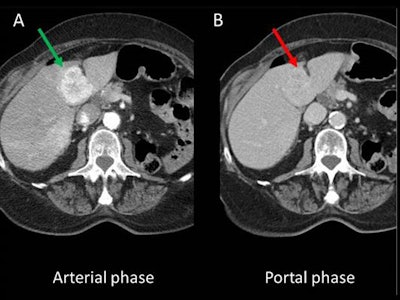

Choosing the most appropriate CT protocol is vital, they stated. For instance, hypervascular metastases are more conspicuous in the arterial phase (see figure).